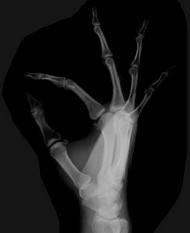

问题 女,41岁,纺织工,腕部痛无力数周,请结合CR和MR,选出最可能的诊断 ( )

选项 A、骨髓炎 B、骨软骨炎 C、月骨缺血坏死 D、骨质疏松 E、月骨结核

答案 C